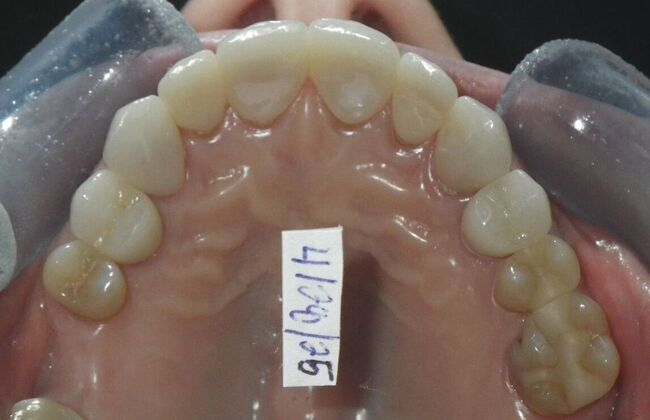

Cosmetic Changes with Veneers and Crown and Bridge: Case 1

Patient presented with spacing between upper central incisors and dark tetracycline stains that she wanted corrected